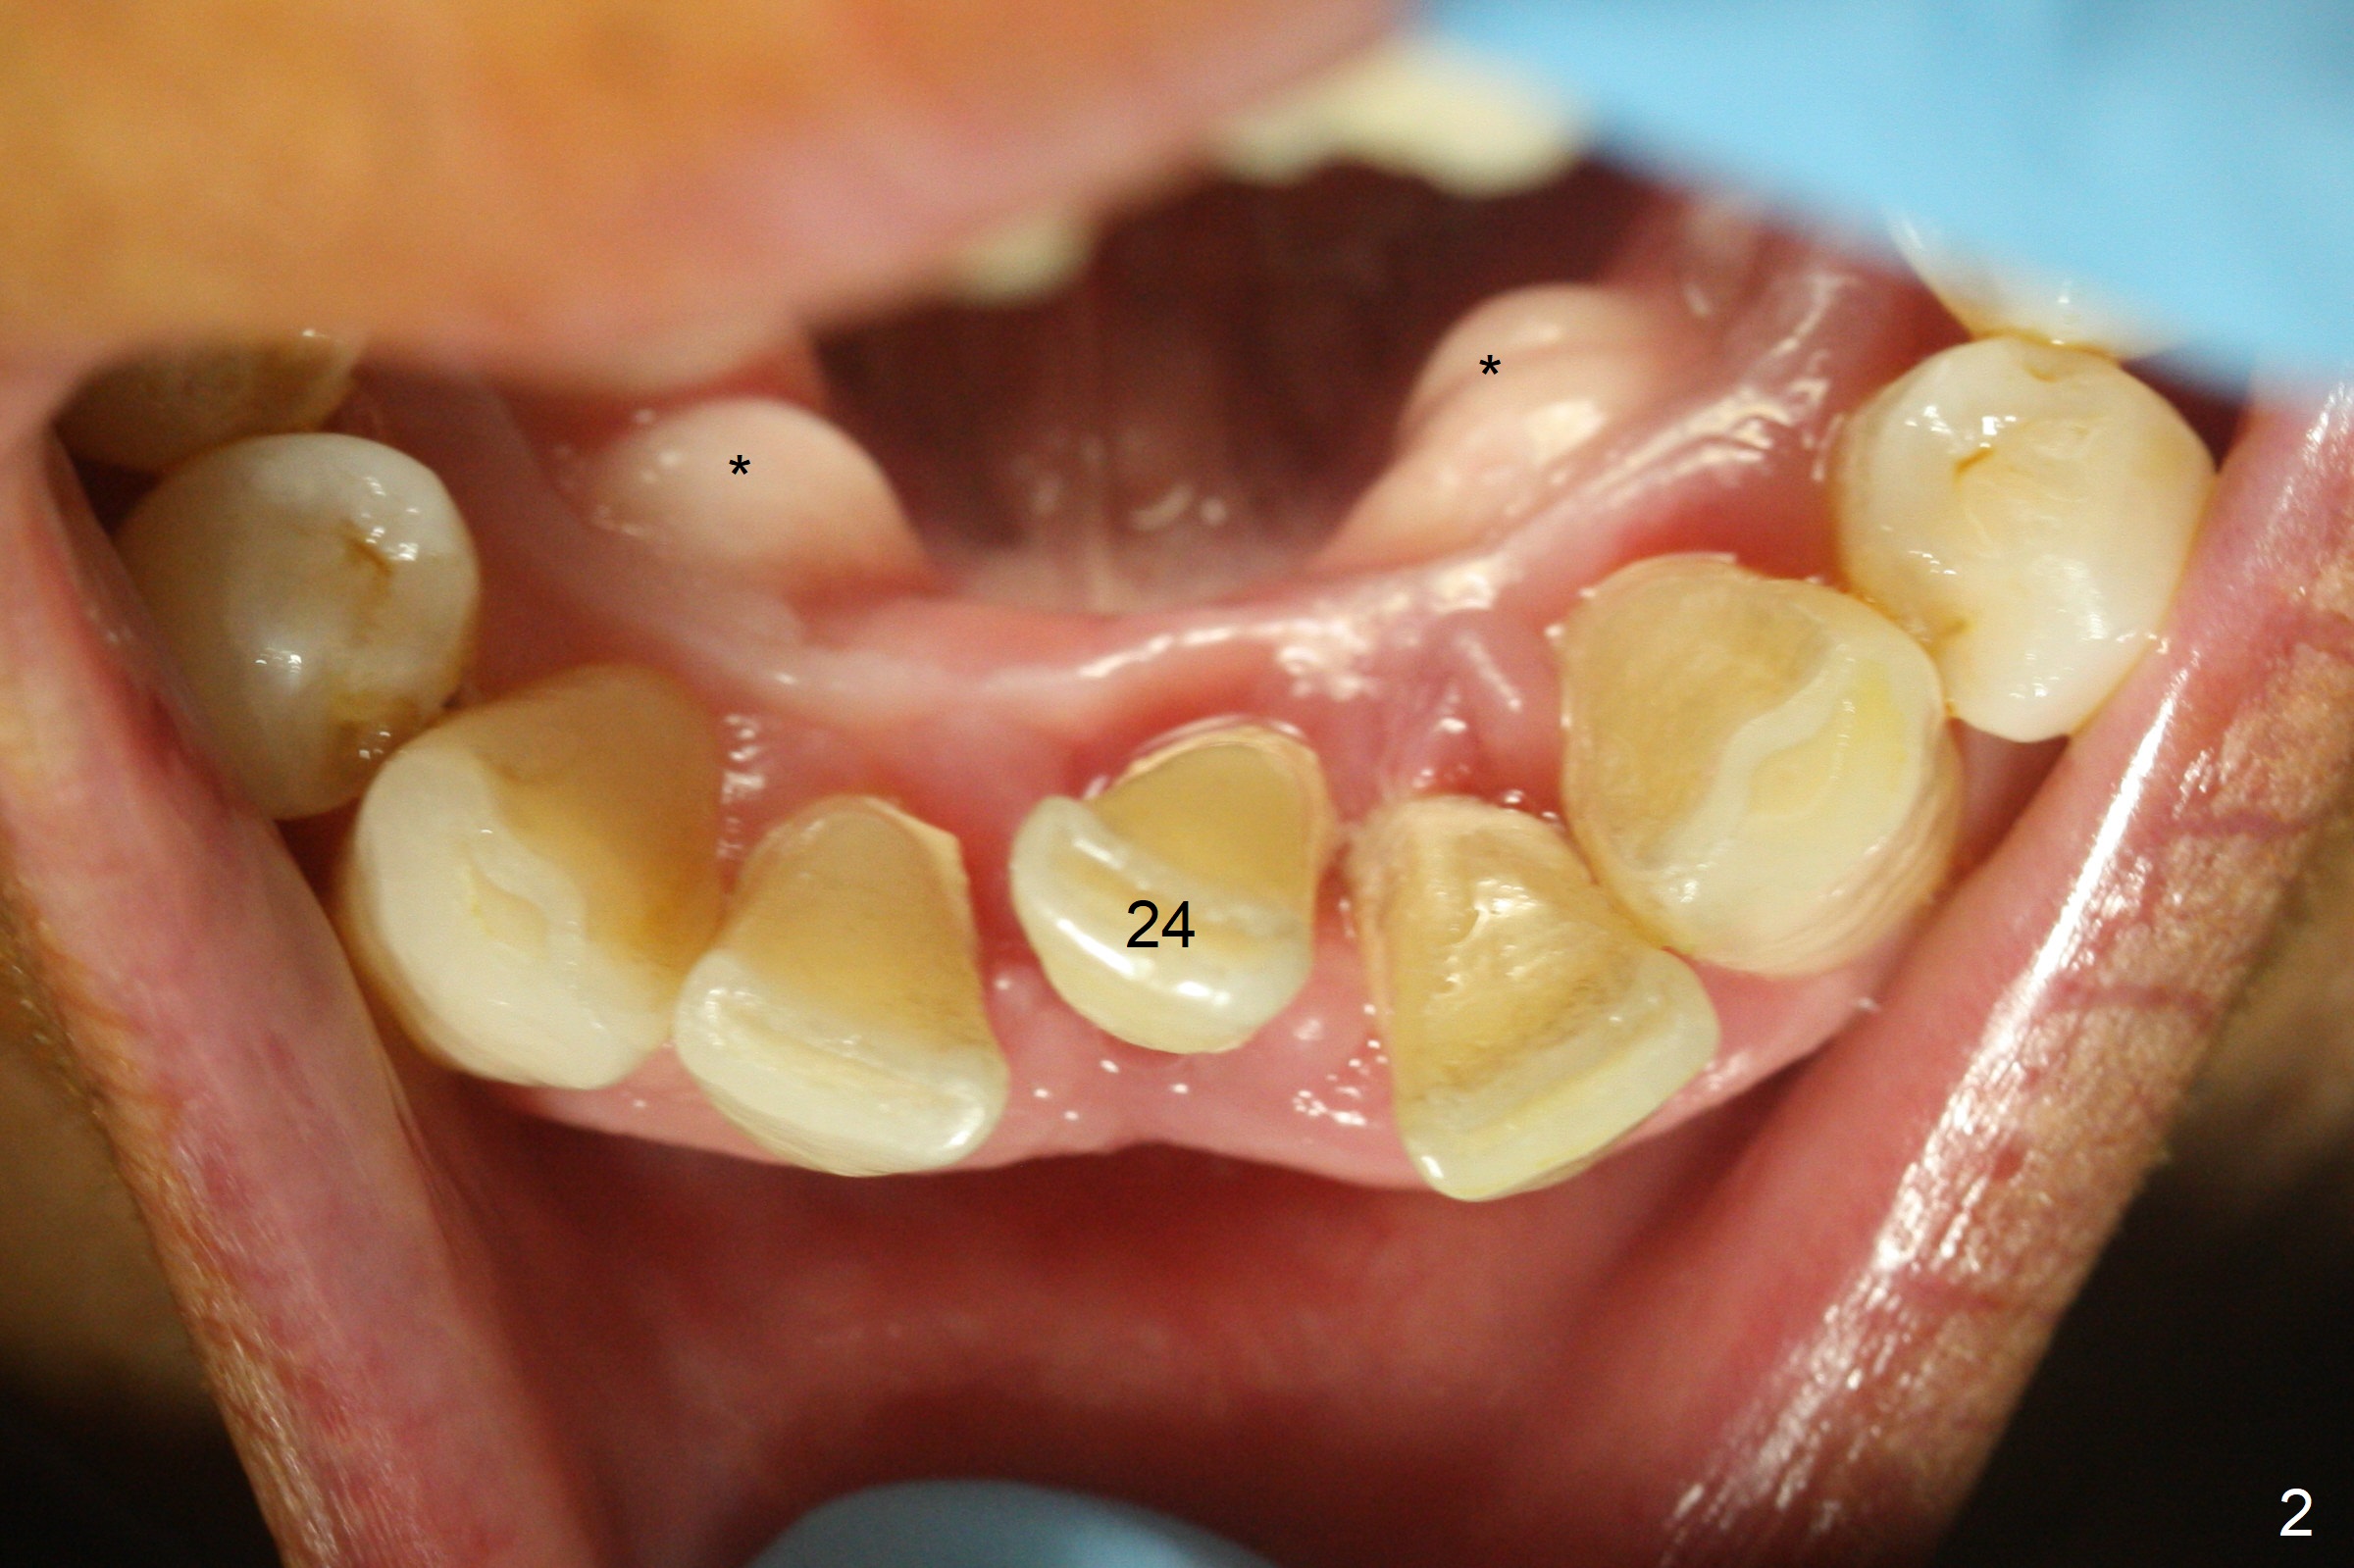

When the patient returns for implant placement 1.5 years after the last treatment (SRP), the tooth #25 has exfoliated, whereas the tooth #24 is severely displaced (Fig.1-3). In fact the buccolingual plates are found to be lost after extraction, corresponding to change in gingival color indicated by an arrowhead in Fig.1. Initial osteotomy with 1.2 mm drill is parallel to the terminal branches of the Incisive Canal (Fig.4 arrowheads). Since the gingiva is as thick as 7.5 mm (Fig.3 arrow), a 3x14 mm 1-piece implant with 4 mm cuff is placed (Fig.5); three implant threads are outside the native bone; with allograft (*) placed and the neighboring crests being coronal to the threads, the chance of periimplantitis should be remote. An immediate provisional is fabricated to contain the graft in place. Meanwhile the tooth #2 is symptomatic with crack. The top 3 threads appear to be contacted by the newly formed crestal bone 6 months postop (Fig.6 *). Bone appears to have grown into the space between implant threads 6 months post cementation (13 months postop).